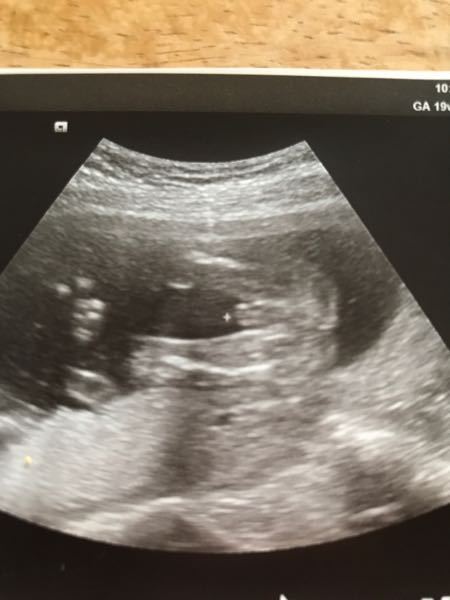

妊娠20週目エコー写真 胎児の大きさや胎動の様子 性別 妊娠中期

19週で性別判明 男の子と確定したエコー写真 かまくら子育てブログ